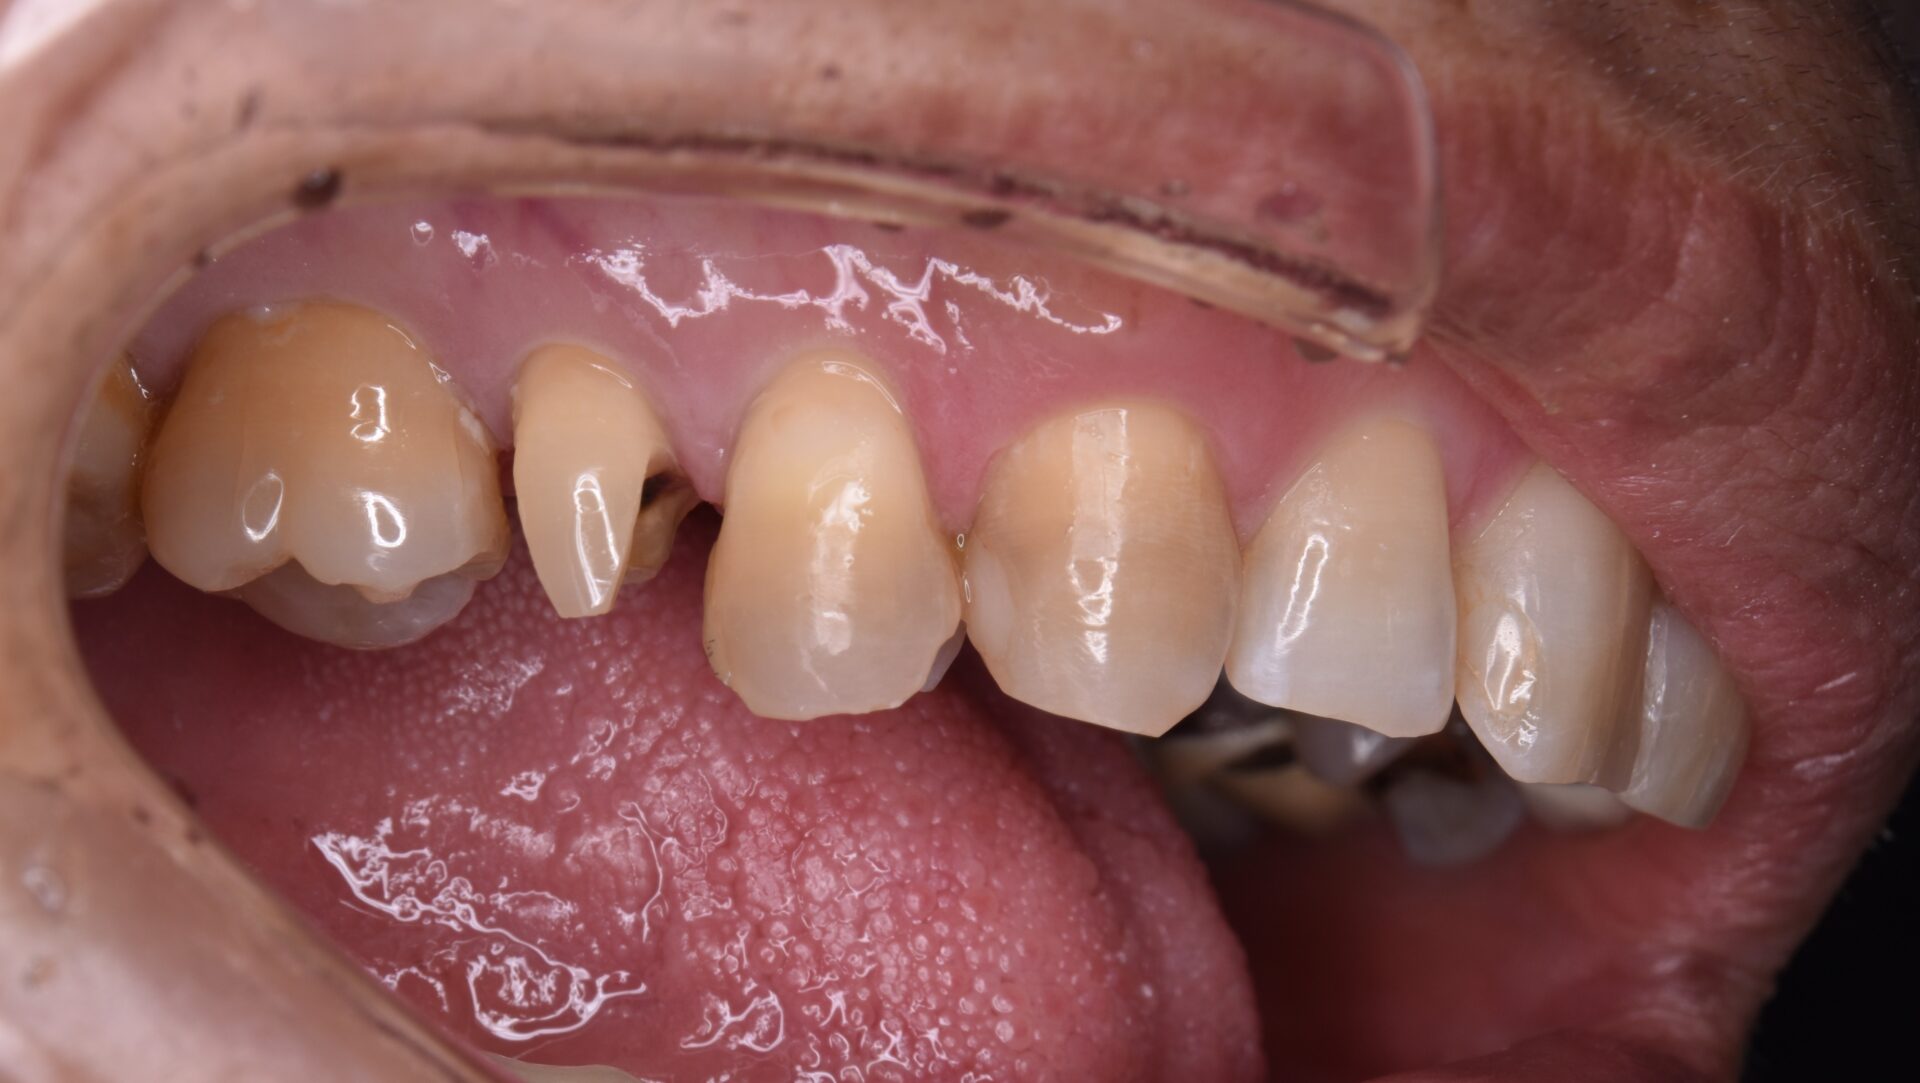

2025年11月14日 審美治療例15 → 患者さんの年齢 54歳 症状 色が気になる 治療内容 セラミックス 費用 13万円 治療期間・回数 2週間・2回 デメリット・リスク 神経を保存して最小限の削合で行う為、破折の可能性あり